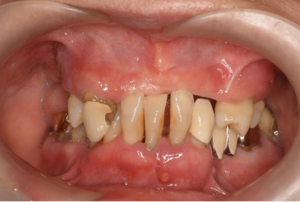

様々な種類の入れ歯から、

あなたに合った入れ歯をご提案します

当院は仮の入れ歯をお作りして、本入れ歯の作製に移ります。仮の入れ歯をお使いの間に見た目の美しさを重視するのか、機能を重視するのかなどをお聞きし、様々な入れ歯をご要望に応じて提案していきます。